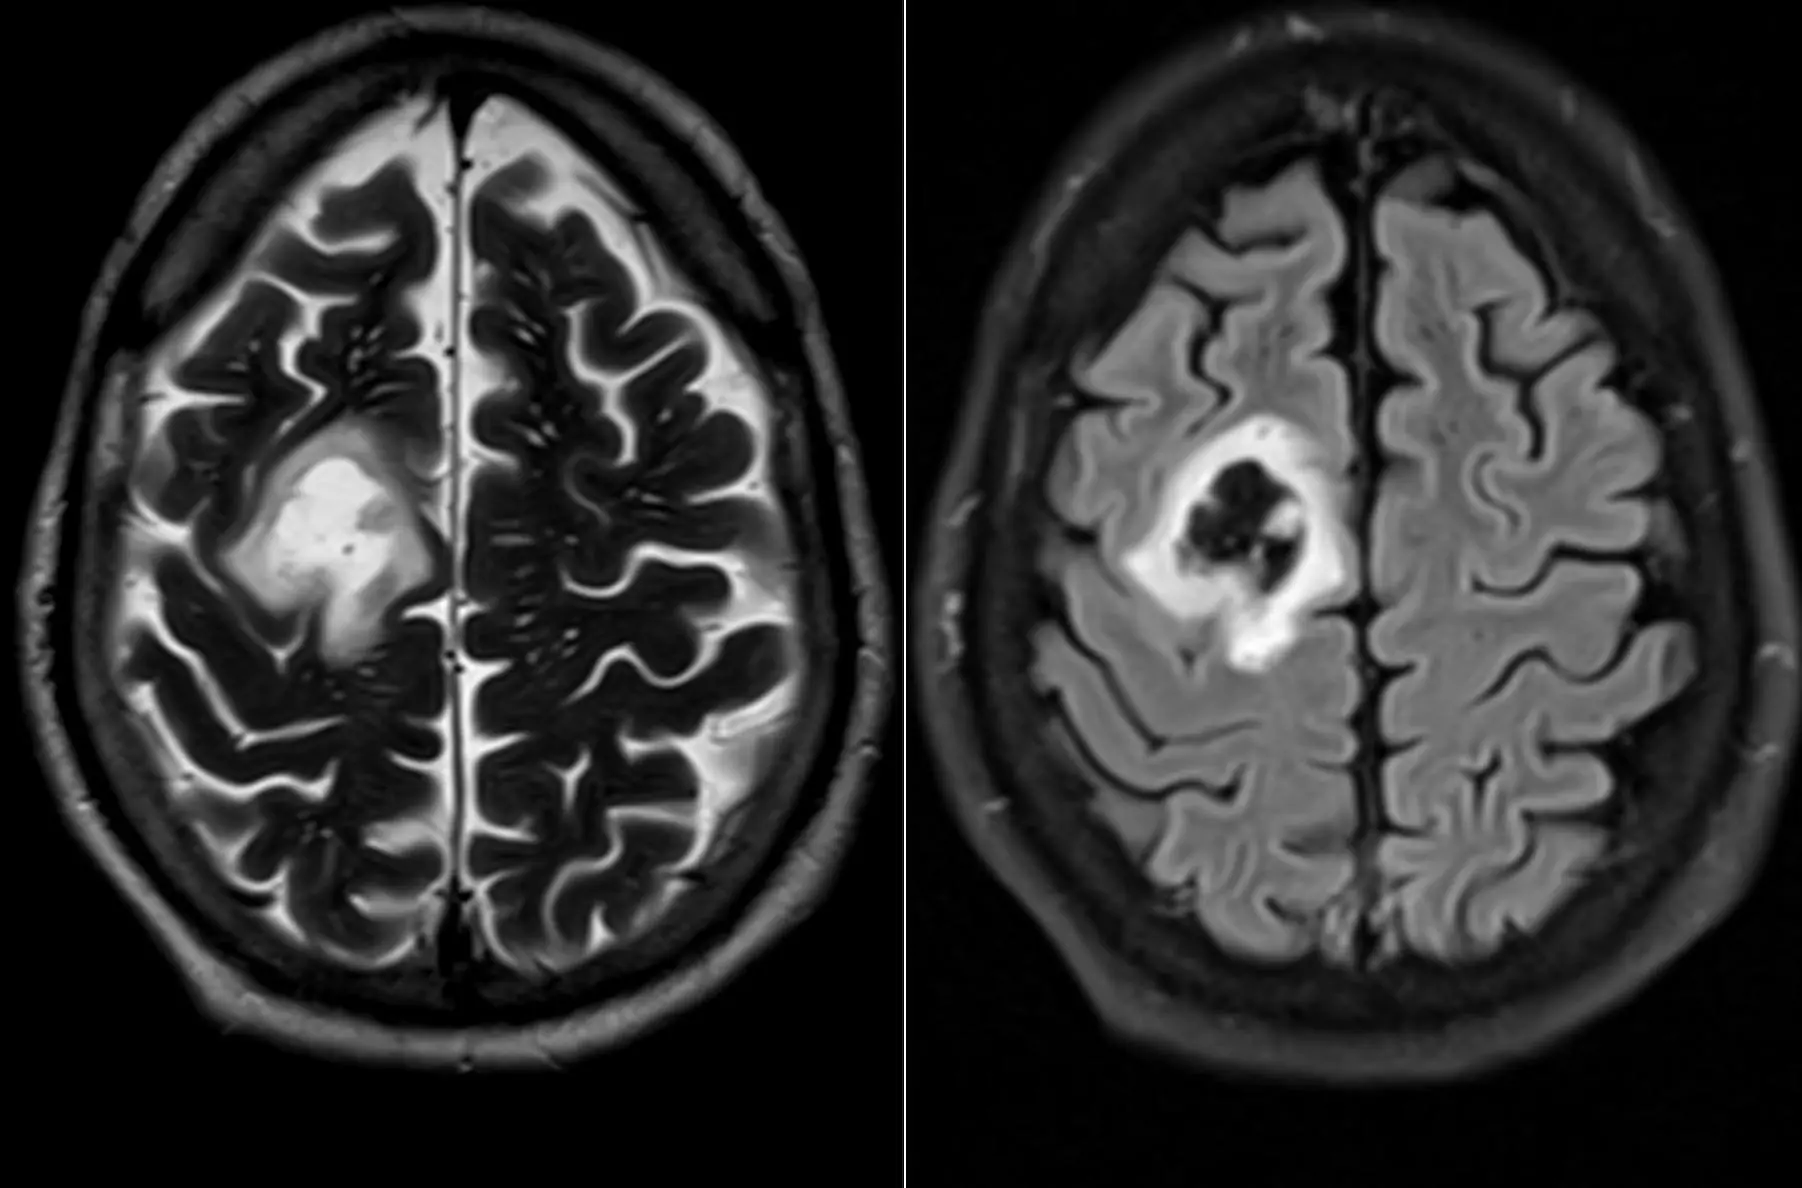

Женщина 32 года. Больной считает себя с 2024 г, когда стала отмечать онемение угла рта. Со слов пациентки ей был предварительно выставлен диагноз - РС, но дополнительных методов обследования и специфического лечения не проводилось. В настоящее время жалоб нет. В исследовании от октября 2024 отмечался очаг в левой затылочной доле с выраженным контрастированием, в настоящее время этот же очаг отмечается с сохраняющимся контрастированием. Формально - есть выполнение критериев диссеминации и в пространстве (юкстакортикальный и перивентрикулярный очаги есть), и во времени (есть усиливающиеся и неусиливающиеся очаги), клиника тоже вполне укладывается. Но! Найти в литературе подобных случаев мне не удалось, видел сам и максимум, что находил в литературе - полгода контрастирования. Получается, мы имеем дело с крайне атипичным рассеянным склерозом, или это не рассеянный склероз. А тогда что? Сосудистая мальформация не вариант - на SWI не видать. Какая-то ганглиоглиома? А другие очаги тогда что? Есть соображения? Кстати, диффузия стойко повышенная, и на б1000 почти не видно (изо). На Т2 не меняется